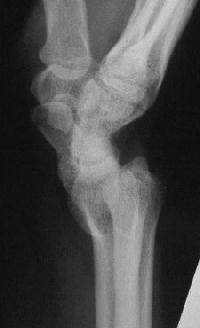

Case 2. Minimal Madelungs picture following pediatric distal radius fracture.